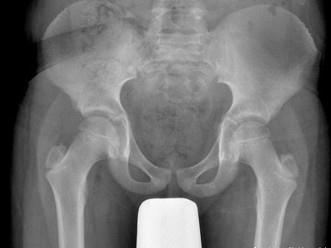

男,请根据其正常骨盆影像图像,判断其最可能的年龄 ( )A、20岁左右B、25岁左右C、10岁左右D、15左右E、5岁左右

问题 男,请根据其正常骨盆影像图像,判断其最可能的年龄 ( )

选项 A、20岁左右 B、25岁左右 C、10岁左右 D、15左右 E、5岁左右

答案 C